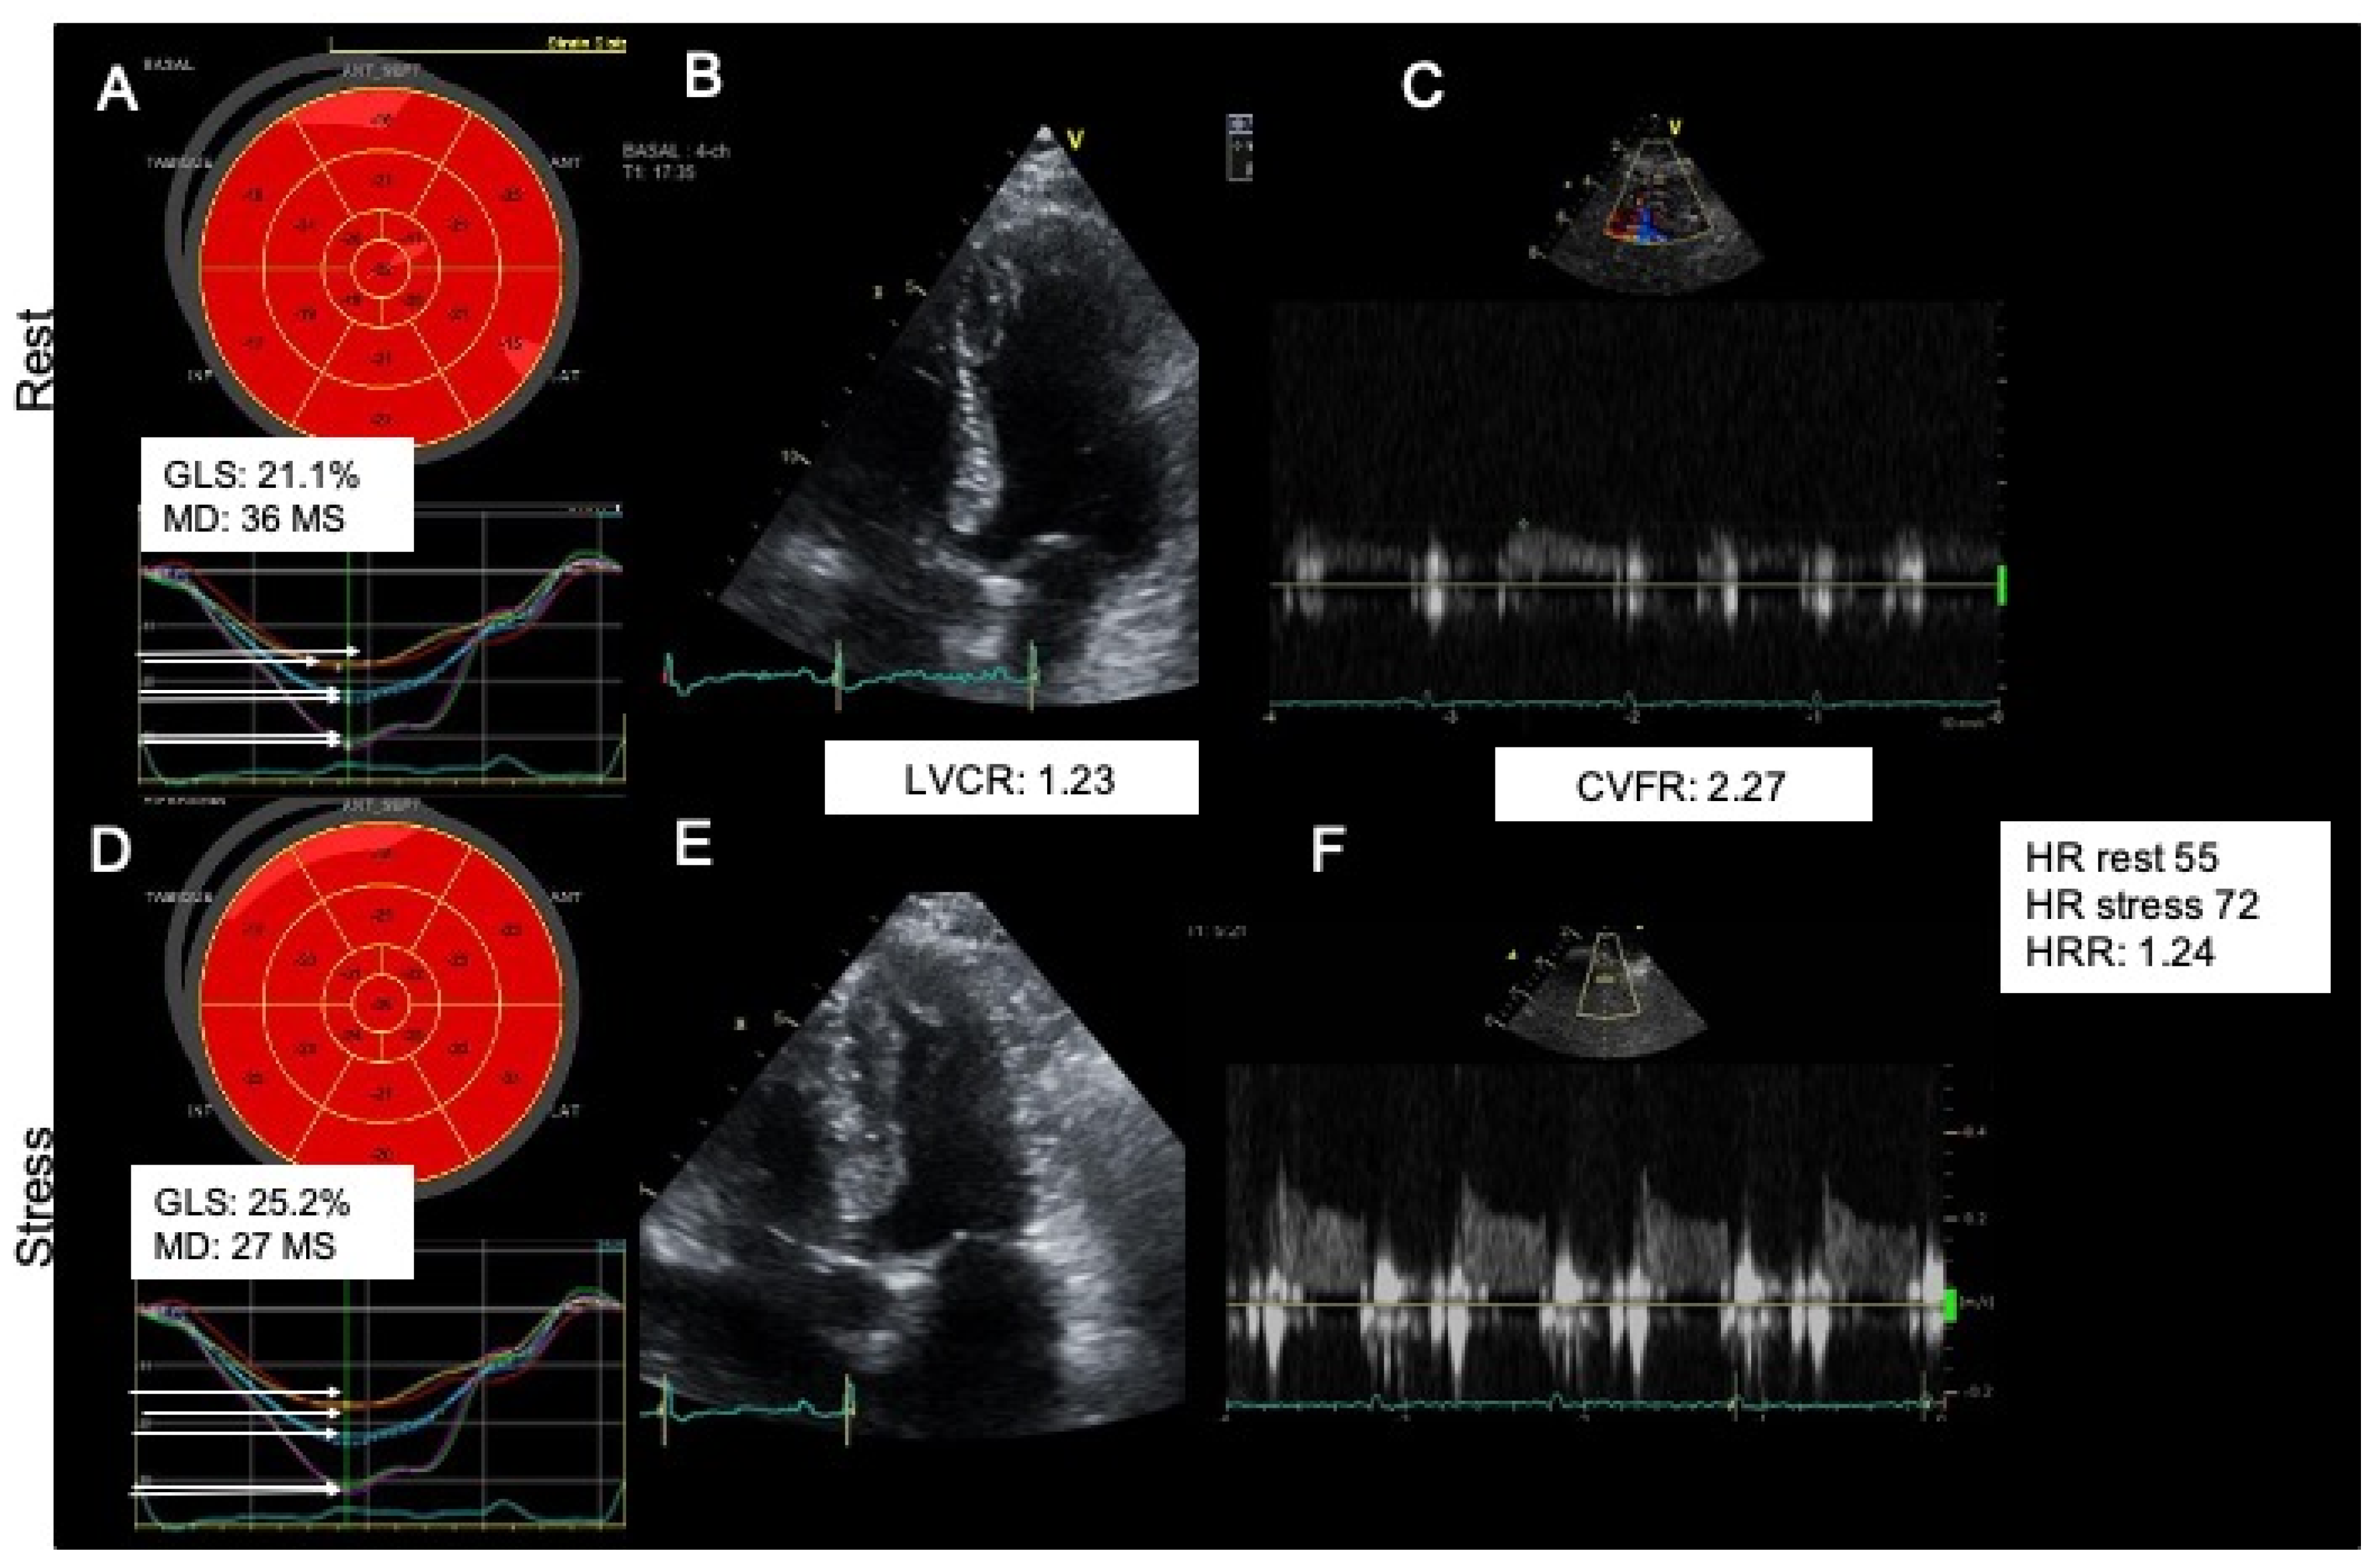

Figure 3 and Figure 4 show examples of a typical response in patients of group 1 (abnormal CVFR) and group 2 (normal CVFR) and their corresponding changes in myocardial mechanics at rest and hyperemia. During vasodilator SE patients with microvascular angina had lower GLS (p = 0.007), higher dyssynchrony by MD (p = 0.0005), and lower LSS both endocardial (p = 0.001) and epicardial (0.0002), whereas LVCR was not different between groups; however, the strain stress-rest delta (<0.0001) and SR (<0.0001) were reduced in patients with INOCA and reduced CVFR. Patients with INOCA and reduced CVFR also had abnormal autonomic function reflected by a reduced HRR (p = 0.044) (Table 4).

Figure 3.

A typical normal response of a normokinetic and strained (A strain normal), dry (B step normal) not shown in the image, strong (C step normal), warm (D step normal) and fast (E step normal) heart. Upper panel shows rest findings: Strain (A), LVCR (B), CVFR (C). Lower panel shows stress findings Strain (D), LVCR (E), CVFR (F). GLS: global longitudinal strain, MD: mechanical dispersion, CVFR: coronary flow velocity reserve, HR: heart rate, HRR: heart rate reserve LVCR: Left ventricular contractile reserve.